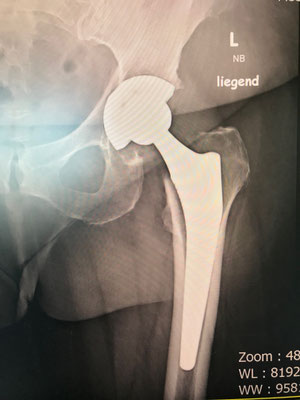

An der Hüfte setzen wir auf langjährig bewährte Implantate, die nachweislich über Jahrzehnte gute Ergebnisse liefern. Wir versuchen, wenn möglich, größere Standardkugeln einzusetzen um eine möglichst gute Beweglichkeit zu erreichen. Leider hatten bisherige "moderne" neue Hüftgelenke immer wieder Probleme, sodaß diese relativ schnell vom Markt wieder verschwanden ( z. B. Roboterhüfte, Computer designed Prothese, Oberflächenersatz).

Jede Hüftprothese wird zuvor, wie in einem Ingenieurbüro am Computer geplant (siehe Bild im Link Praxis) und ausgemessen, um diese Werte möglichst in der Operation umzusetzten. Ziel ist es, ihr eigenes Gelenk so zu ersetzen, daß ihr Muskelzug und Kraftübertragung erhalten bleibt und die Prothese optimal eingepaßt wird.